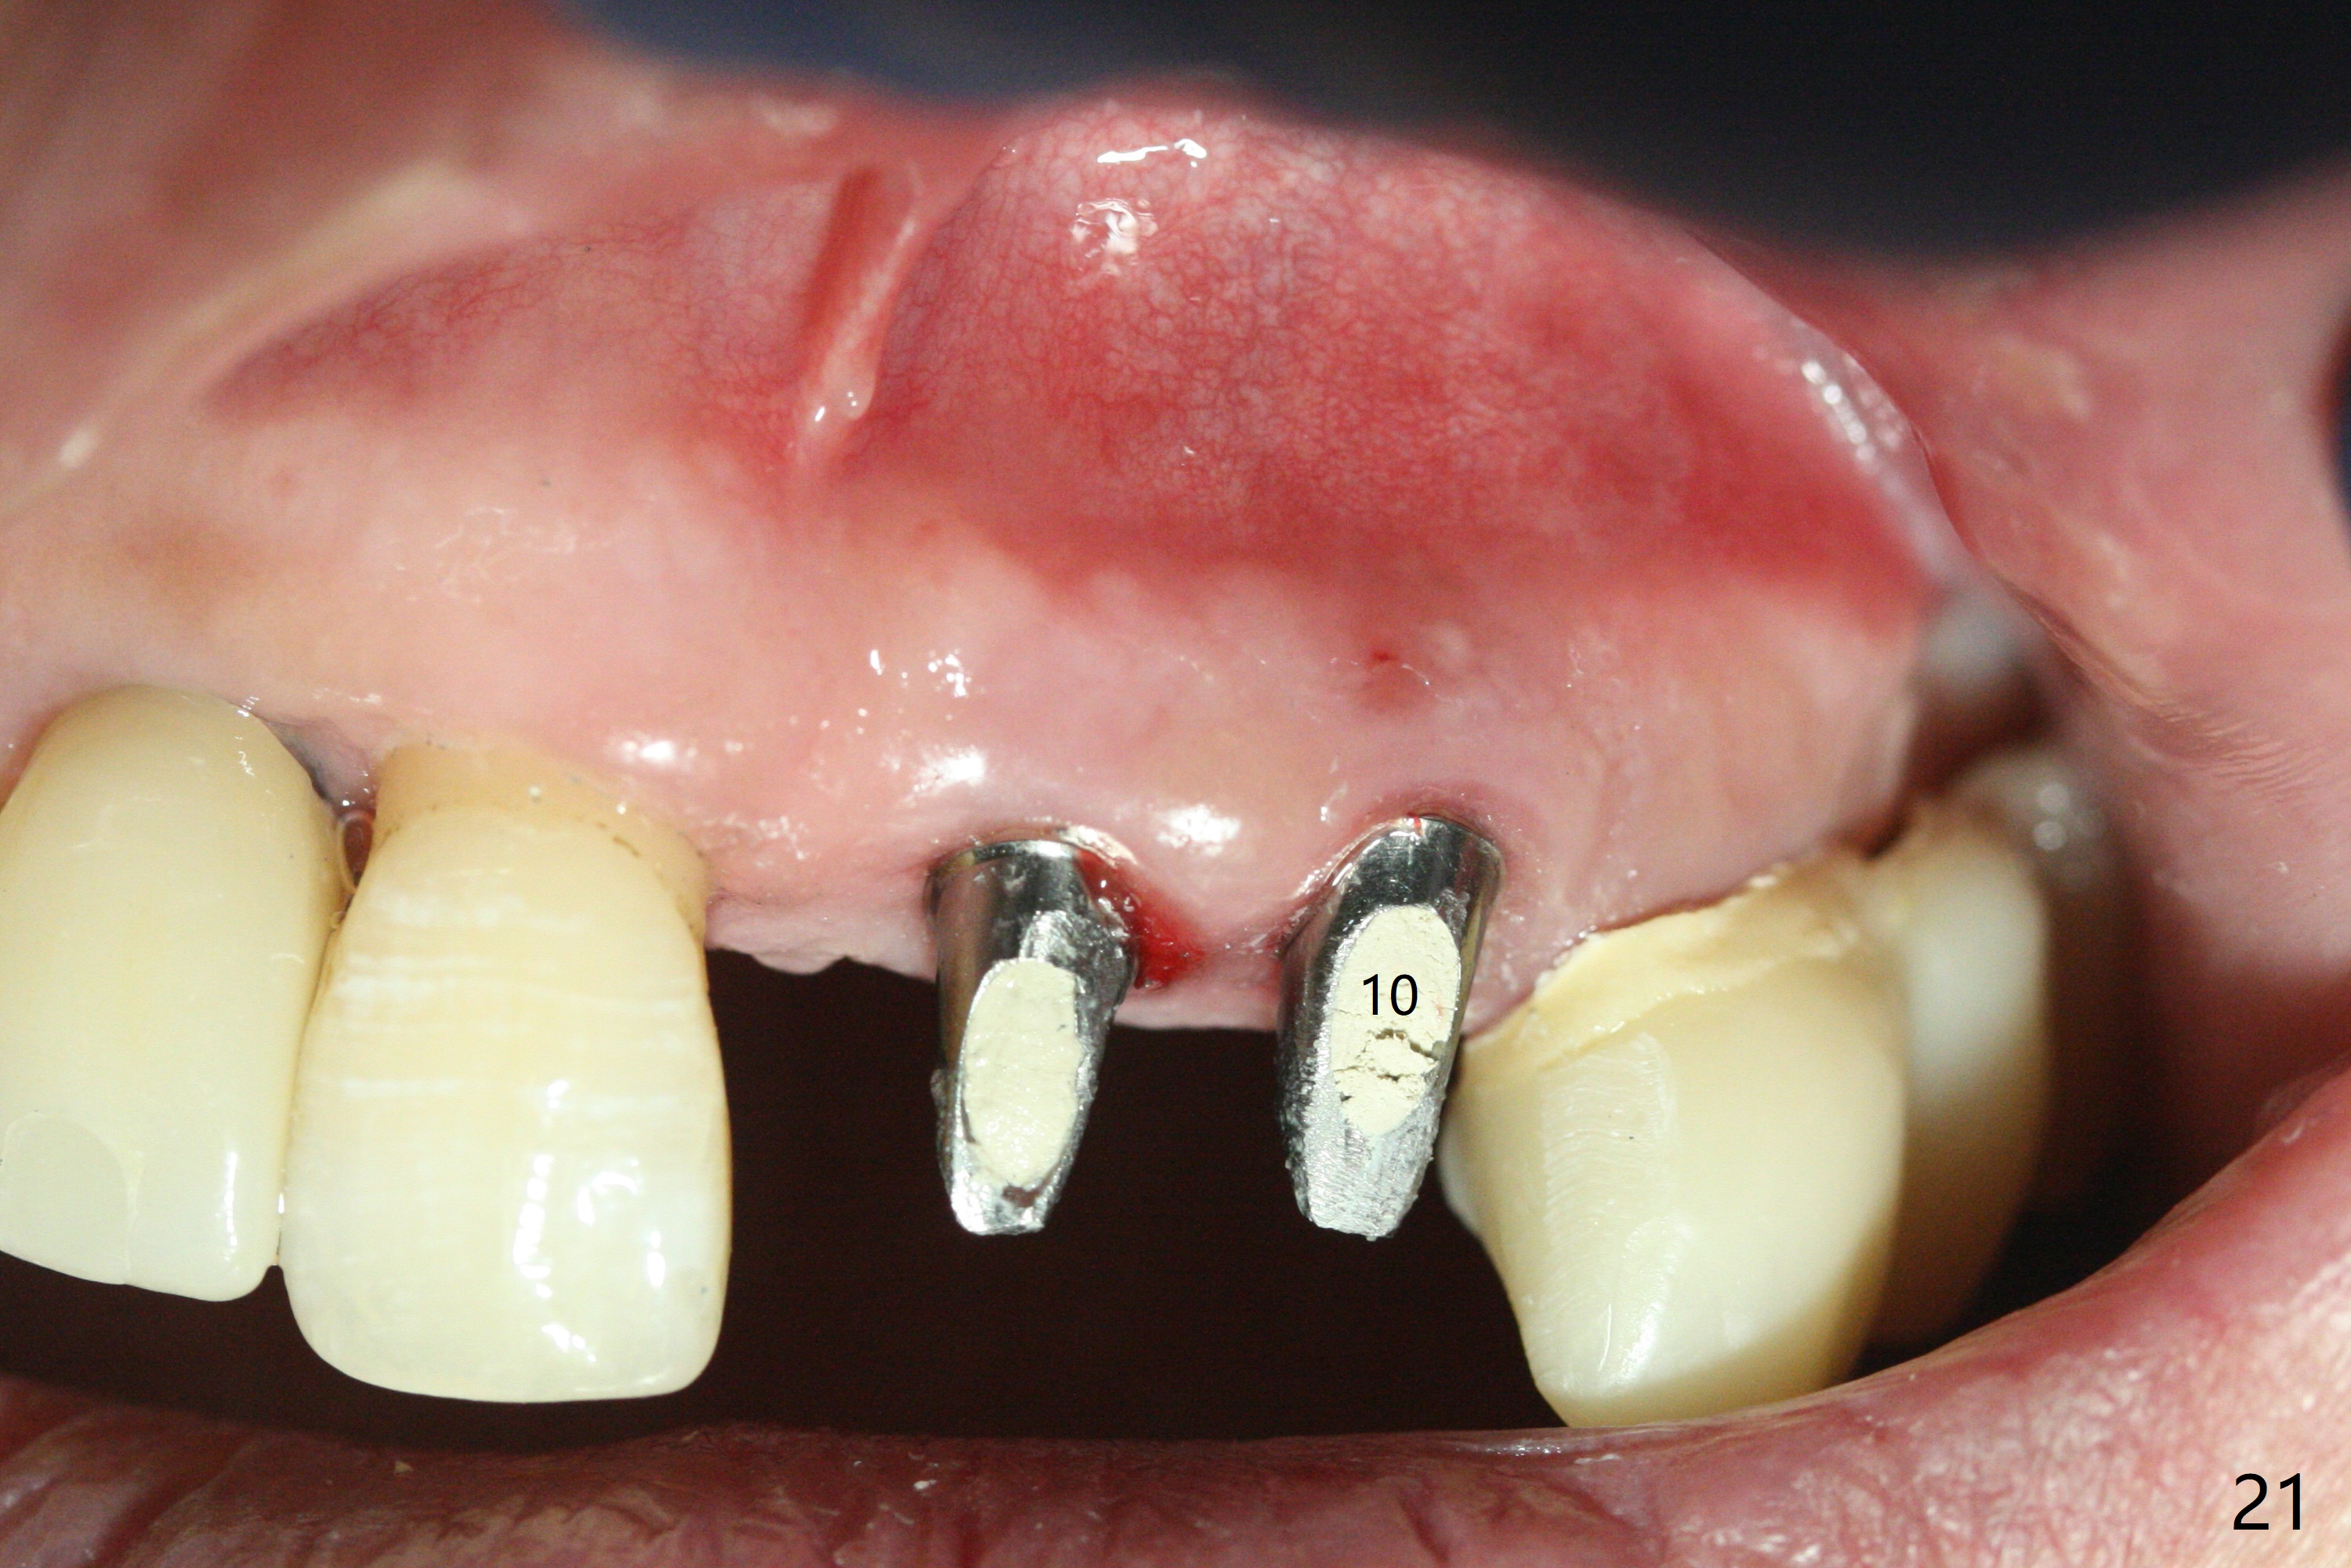

The patient returns 8 days postop, uncomfortable with overhang in the provisional (Fig.10 *). The sockets appear to be healing with loose bone graft (Fig.11) when the provisional is removed for trimming (Fig.12). Six (for #7,13) and seven (#9-11,15) months postop, the soft (Fig.13,17) and hard (Fig.14-16,18) tissues heal. It appears that the trajectory at #9,11 and 13 should be changed by using angled abutments (Fig.18,19 (panoramic X-ray taken 2 months earlier)) before provisional and final restoration.